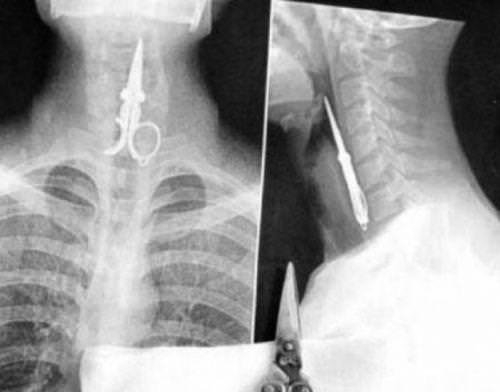

Röntgen filmlerinden çıkan akıl almaz şeyler

Hastane koridorlarına düşenler bilir… Doktora görün, tahlilleri yaptır, röntgenleri çektir falan filan derken insanın ömründen ömür gider. Gelin görün ki bu sefer çektirilen röntgenlerde öyle ilginç şeyler çıkmış ki ağzımız açık kaldı…